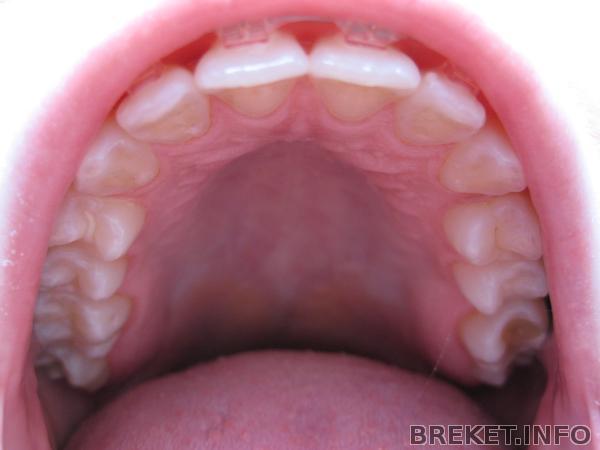

На ВЧ одели чейн почти на всю челюсть, потому что с одной стороны тоже небольшой промежуточек есть.

Вобще орта сказала, что закрывать все будем перед самим снятием и закреплять ретейнерами и пластинками.

С функциональной частью мы закончили и в принципе можно уже просто стянуть все зубы, чтобы убрать щели и снимать (это радует конечно). НО теперь будем работать над "красотой", т.е. над тем, что НЕ нравится лично МНЕ. Радостно, что орта не настаивает на снятии и дает время поработать над эстетикой, чтобы мы не жалели о снятии.

Сегодня Panika писала про параллельность дуг..у меня ее даже а помине нет!